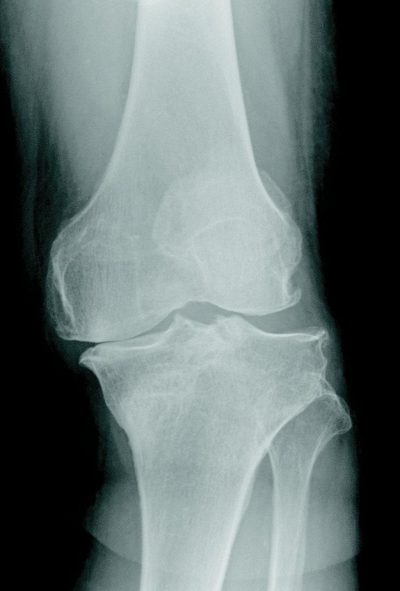

身長 155 cm、体重 64 kg。体温 36.3 ℃。脈拍 64/分、整。左膝関節に膝蓋跳動と内反変形とを認めるが発赤と熱感はない。左膝関節エックス線写真を別に示す。